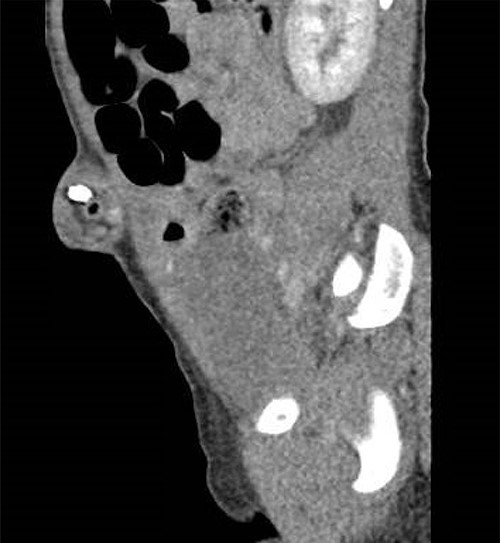

Her laboratory results demonstrated a leukocytosis with a left shift 11.27. Abdominal x-ray and CT imaging studies from the outside ED were reviewed and showed bowel obstruction with radiopaque objects near the neck of the hernia (Fig. 1). Attempts at manual reduction of the umbilical hernia were unsuccessful and the decision was made to proceed to the operating room for an umbilical exploration.